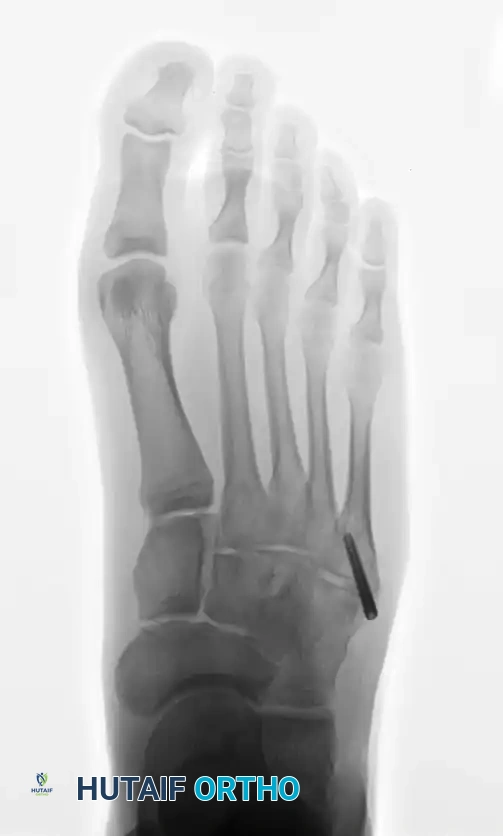

PREOPERATIVE PLANNING AND IMAGING

Standard weight-bearing anteroposterior (AP), lateral, and oblique radiographs of the foot are mandatory. The oblique view is particularly useful for profiling the fracture line at the metaphyseal-diaphyseal junction.

In cases of delayed union or nonunion, advanced imaging such as a Computed Tomography (CT) scan may be warranted to assess the extent of medullary sclerosis and to precisely measure the canal diameter. The medullary canal of the fifth metatarsal is not perfectly straight; it exhibits a lateral and plantar bow. Preoperative templating is critical to select a screw diameter that achieves cortical purchase without causing iatrogenic lateral cortical blowout.

- Fluoroscopic Confirmation: Advance the wire under multi-planar fluoroscopy. Ensure the wire passes the fracture site and sits centrally within the narrowest portion of the diaphysis (the isthmus).

- Confirm the drill's location via AP and lateral radiographs. The drill should cross the fracture site and engage the diaphyseal cortex without breaching it.

- Verify final screw placement, fracture reduction, and compression with orthogonal radiographs.